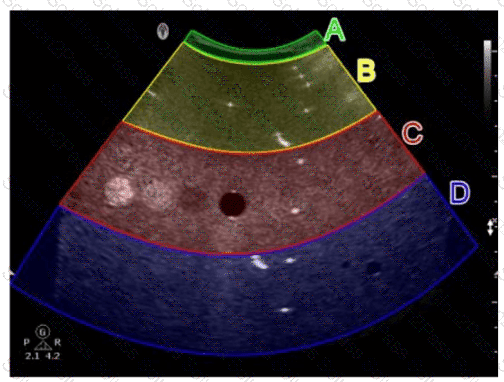

In this image obtained from a tissue-mimicking phantom, which area of the sector is used to evaluate the dead zone?

A.

Option A

B.

Option B

C.

Option C

D.

Option D